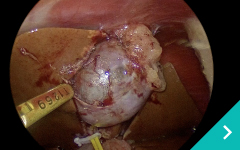

ミニマム創内視鏡下手術は腹腔鏡だけでは対処ができないような手術の際に、お腹にラッププロテクターという器具を設置して行う腹腔鏡と開腹手術を組み合わせた手術です。

『傷』が小さく、『痛み』が少ない手術・検査ができます!!